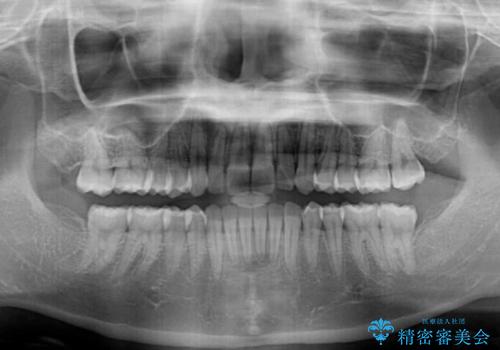

- 上下前歯のデコボコと深い咬み合わせを気にして来院された患者様です。

インビザラインによる上下歯列の拡大と、IPR(歯と歯の間を削る)にるスペースの獲得により、前歯のデコボコを改善することとしました。

上の前歯をもう少し整えたかったのですが、患者様の治療を早く終了させたいという希望により、細かい叢生を残しての終了となりました。